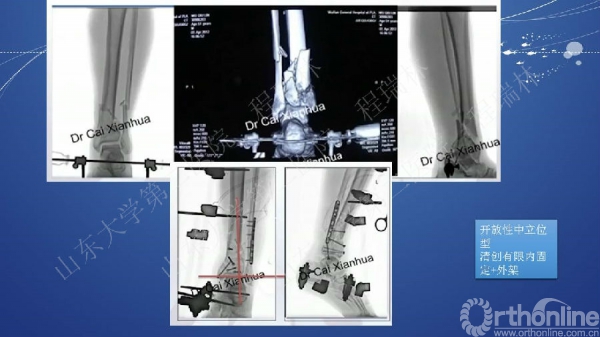

Pilon骨折的手术基本原则

Pilon骨折是踝部的复杂骨折,以高能量损伤、不稳定、软组织损伤严重为特点。手术复杂,并发症常见且严重。一旦治疗失败,常常带来灾难性的后果,如截肢、严重创伤性关节炎后期再关节融合等。

Pilon骨折的治疗目的:软组织保护,恢复下肢力线,解剖复位关节面。